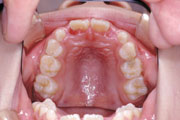

症例2:乱杭歯(叢生)